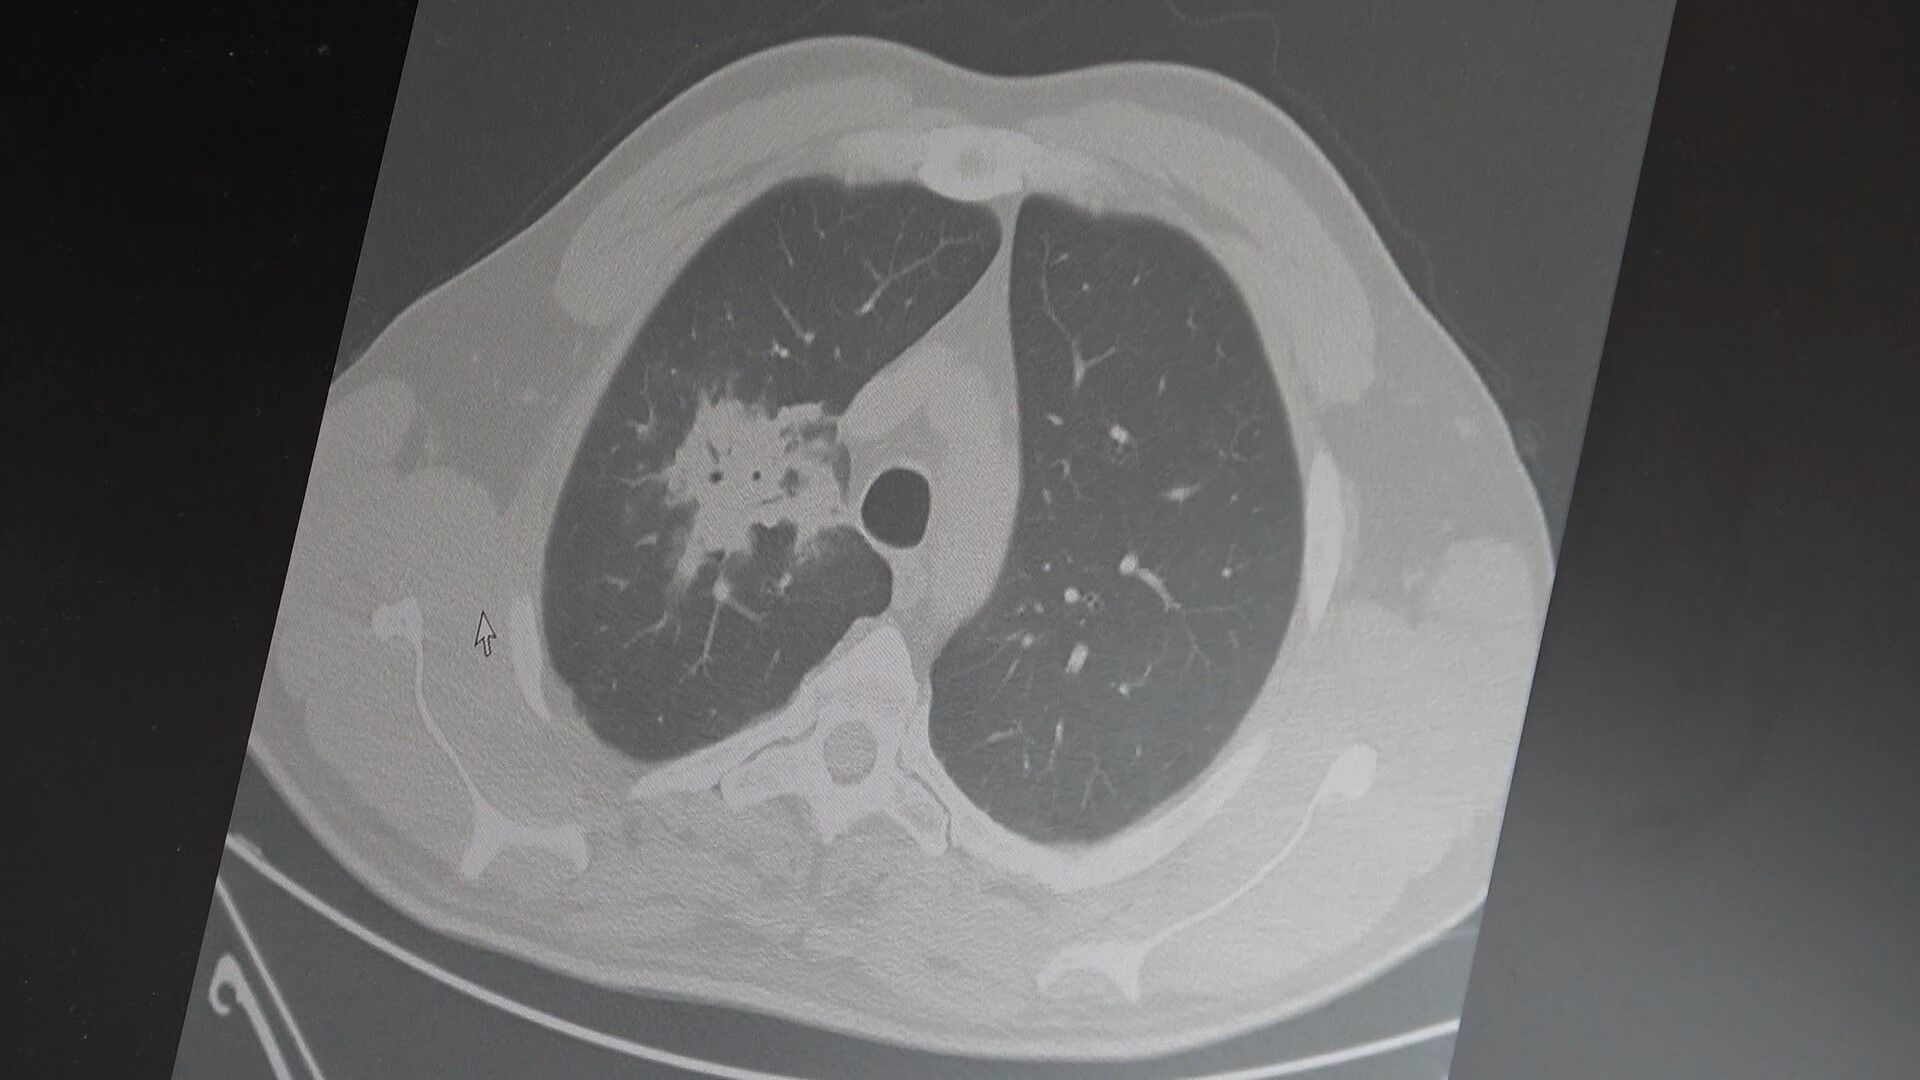

Son yıllarda yapılan 100’den fazla bilimsel çalışmanın analiz edildiğini vurgulayan Özkaya, elektronik sigaraların özellikle akciğer ve ağız dokularında kanser riskini artırabileceğine dair güçlü bulgular bulunduğunu söyledi. Araştırmalarda insan, hayvan ve laboratuvar verilerinin birlikte değerlendirildiğini belirten uzman isim, elektronik sigara içeriğindeki kimyasalların hücre düzeyinde ciddi zararlara yol açtığını dile getirdi.

2024 yılında yayımlanan bilimsel bir çalışmaya da değinen Özkaya, hem geleneksel sigara hem de elektronik sigara kullanan bireylerde riskin daha da arttığını belirtti. Buna göre, çift kullanımın akciğer kanseri riskini yalnızca sigara içenlere kıyasla yaklaşık dört kat artırdığına dikkat çekildi.